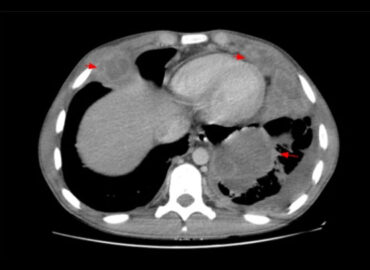

Hombre – 38 años Profesor de bonsai Sin APP relevantes MC: dolor en hipocondrio derecho EF: dolor a la […]